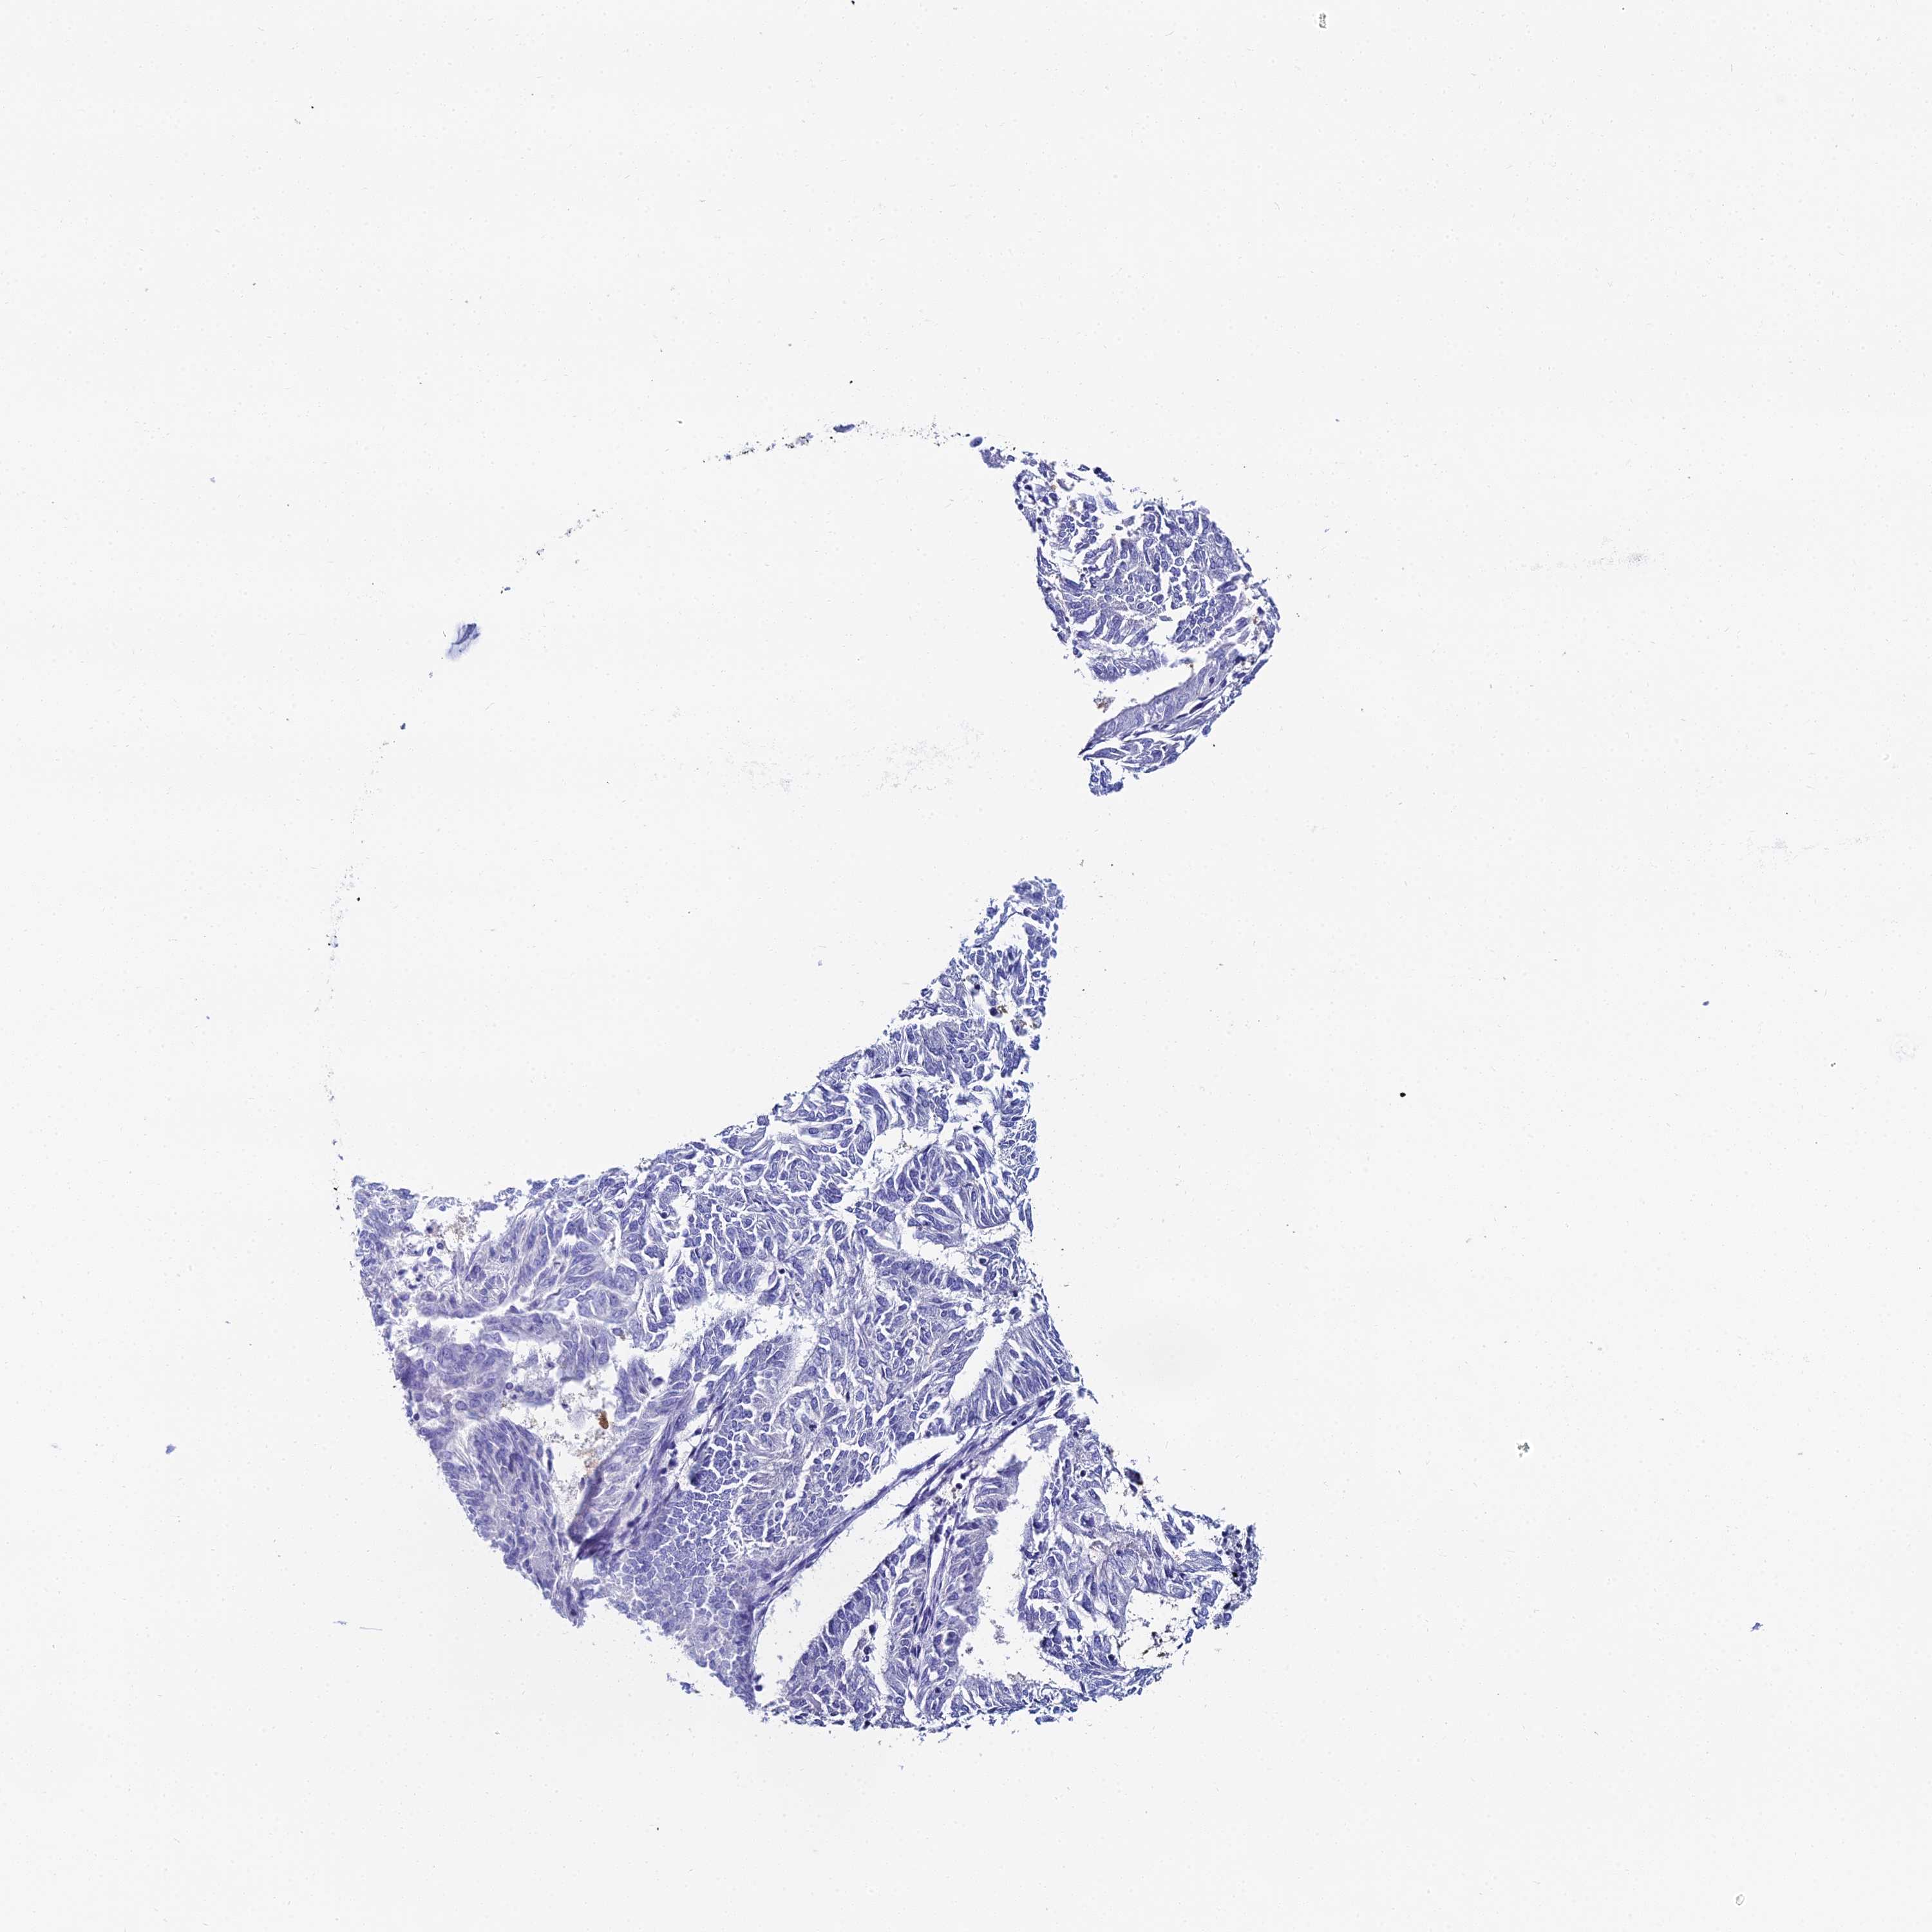

ENDOMETRIAL CANCER - Protein expressioni

A mouse-over function shows sample information and annotation data. Click on an image to view it in a full screen mode. Samples can be filtered based on level of antibody staining by selecting one or several of the following categories: high, medium, low and not detected. The assay and annotation is described here.

Note that samples used for immunohistochemistry by the Human Protein Atlas do not correspond to samples in the TCGA dataset.

Antibody stainingi

Antibody staining in the annotated cell types in the current human tissue is reported as not detected, low, medium, or high, based on conventional immunohistochemistry profiling in selected tissues. This score is based on the combination of the staining intensity and fraction of stained cells.

Each image is clickable and will lead to virtual microscopy that enables deeper exploration of all samples and also displays staining intensity scores, fraction scores and subcellular localization as well as patient and tissue information for each sample.

Antibody HPA043285

Antibody HPA052504

Staining

High

Medium

Low

Not detected

Intensity

Strong

Moderate

Weak

Negative

Quantity

>75%

75%-25%

<25%

None

Location

Nuclear

Cytoplasmic/membranous

Cytoplasmic/membranous,nuclear

Adenocarcinoma, NOS

Adenocarcinoma, metastatic, NOS

Carcinoma, NOS